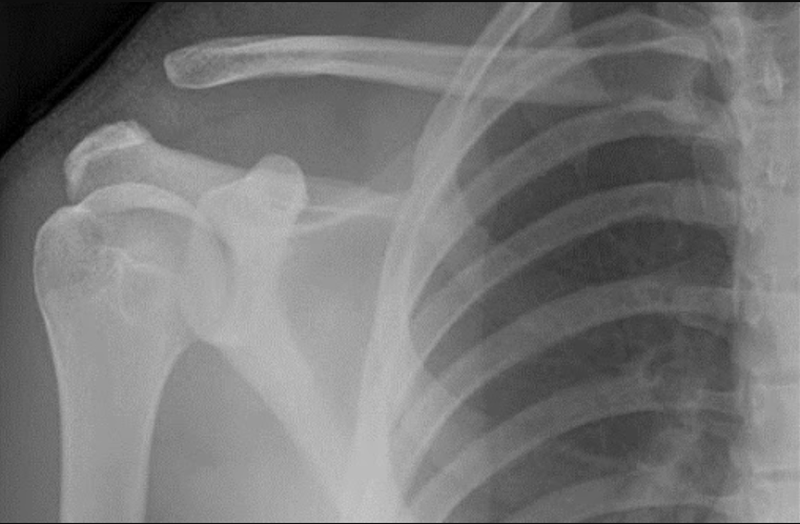

Việc chẩn đoán trật khớp cùng vai đòn dựa vào các triệu chứng lâm sàng và biểu hiện trên X - Quang để đưa ra kết luận chính xác.

Chụp X - quang vai hiện có ở 3 vị trí: chụp X-quang vai thẳng, X - quang chữ Y và X - quang dưới cánh tay.

X-quang Zanca: Tương tự như chụp X-quang vai thẳng, nhưng chùm tia được bắn một góc 10 độ so với đầu. Kỹ thuật này giúp nhìn rõ hơn phần đầu của khớp.

Chụp X - quang stress: Chụp X-quang đường thẳng với quả tạ 4 - 6kg trên tay.